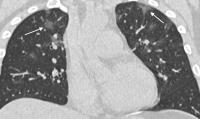

image: 29-year old male with unknown exposure history, presenting with fever and cough, ultimately requiring intensive care unit admission. (a) Axial thin-section non-contrast CT scan shows diffuse bilateral confluent and patchy ground-glass (solid arrows) and consolidative (dashed arrows) pulmonary opacities. (b) The disease in the right middle and lower lobes has a striking peripheral distribution (arrow). view more

The analysis showed that 2019-nCoV typically manifests on CT with bilateral ground-glass and consolidative pulmonary opacities. Nodular opacities, crazy-paving pattern, and a peripheral distribution of disease may be additional features helpful in early diagnosis. The researchers also noted that lung cavitation, discrete pulmonary nodules, pleural effusions and lymphadenopathy are characteristically absent in cases of 2019-nCoV.